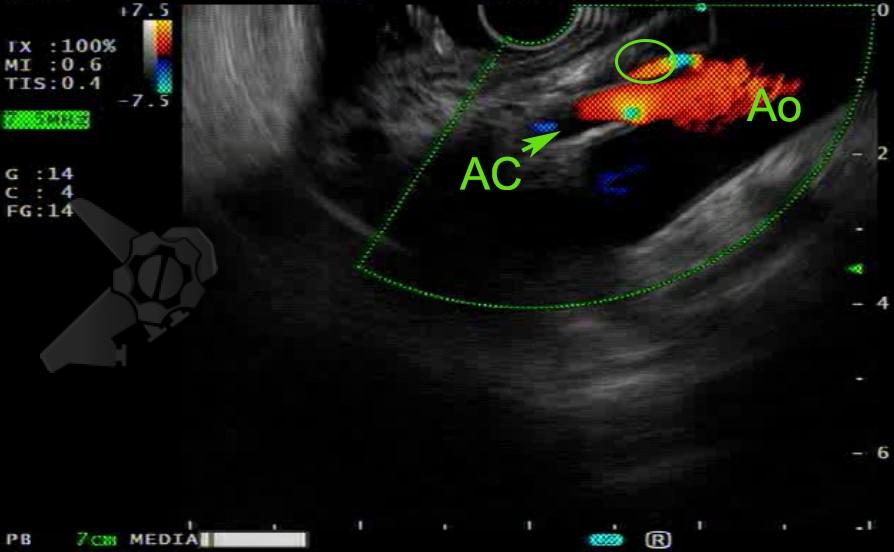

Masculino, 88 anos, aposentado, apresentando quadro demencial leve, assintomático, foi encaminhado ao serviço de endoscopia após a ingestão acidental de sua prótese dentária fixa. O incidente ocorreu há 15 dias, sem eliminação do objeto nas fezes desde então. Ele buscou atendimento na unidade de emergência de sua cidade, onde uma radiografia revelou a presença do objeto na topografia da fossa ilíaca direita (foto 1). Ao exame físico, não havia alterações relevantes com palpação do abdome inocente.

Após preparo colônico com manitol e a realização de uma nova radiografia, que não apontou qualquer mudança na posição inicial da prótese dentária desde a admissão, o paciente foi submetido a colonoscopia. Até a intubação cecal o corpo estranho não foi encontrado, com presença de doença diverticular no hemicólon esquerdo (foto 2 e 3).